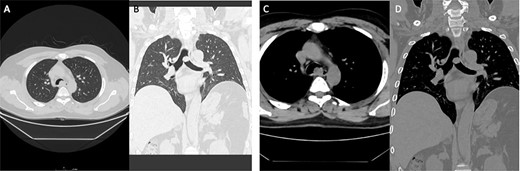

The second case involved a 46-year-old male, who was a smoker for 15 years, however, had quit smoking for 1 year prior to presentation, otherwise medically and surgically free. He had a main complaint of periodic hemoptysis. This patient’s CT scan (Fig. 2) showed a 2.2 × 2 cm lesion at the level of the carina. Operatively, the lesion was resected en bloc in a similar fashion to the first portrayed case, using a combination of bronchoscopic snare and electrocautery. Pathology revealed an endotracheal typical carcinoid tumor (Fig. 1; case 2).

Case 2: panels (A and B) show an intratracheal soft tissue mass just above the carina more toward the left side. (C and D) Same lesion on axial cuts with radiological evidence of infiltration/invading left lateral wall of the trachea.